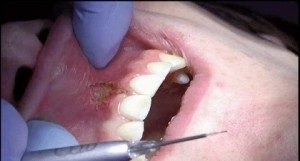

So what can soft-tissue lasers do? Probably a lot more than you think. First, diode lasers can cut and shape soft tissue, which gives us the opportunity to remove lesions, (fibromas), release frenoms, recontour gingiva, and trough around crown preps. Usually this can be accomplished with little bleeding, minimal collateral tissue damage, and better healing. Unlike an electro- surge unit, diode lasers can be used around crowns, ortho brackets, and implants. Diode lasers can also be utilized to whiten teeth. Diode lasers seek pigment so it makes sense that they would be effective at removing pigment and stain in the whitening procedure. I feel the results are similar or better than any in-office whitening system available, with less sensitivity and a shorter appointment time. (I have seen great results in as little as ten minutes utilizing a laser to whiten teeth.)

Certain diode lasers are FDA approved to help treatment of TMD and facial muscle pain. Diode laser can actually penetrate tissue and increase blood flow, decrease edema, and aide in healing. Although diode lasers have been used for many years in treating muscle and joint pain, this could provide another avenue in treating our patients. Diode lasers have been used to help treat periodontal disease and certain studies have shown better results and advantages of utilizing a diode laser in conjunction with scaling and root planning. These studies have shown reduction in bleeding on probing and reduced pocket depth. Other uses for diode laser include treating aphthous ulcers, desensitizing teeth, pulpotomy procedures and, best of all, removing inflamed excess tissue that makes taking your crown impression impossible.